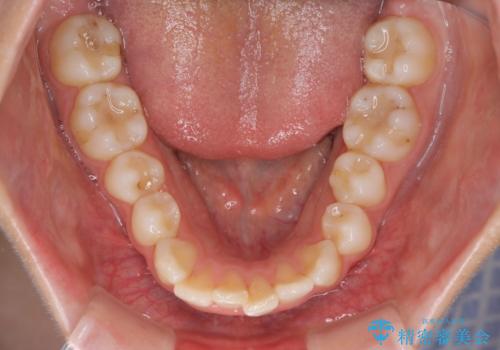

【インビザライン】前歯のガタガタをなおしたい。

- 前歯の凸凹を主訴に来院されました。

インビザラインにて奥歯の遠心移動を行いながら、前歯のガタガタを改善することができました。